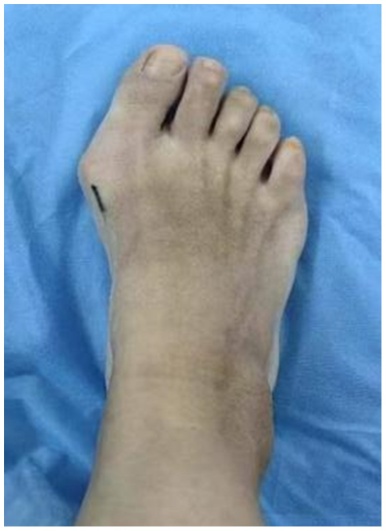

患者女,46岁。因“右足进行性行走疼痛、伴踇趾外翻畸形8月余”来我科就诊。专科检查:右侧第一跖趾关节外翻畸形(见图1(a)图1(b)),活动受限,拇囊部位压痛明显,无纵向叩击痛。第一跖趾关节松弛,活动后疼痛加重。前足功能AOFAS评分为45分,神经血管检查正常,其余肢体未见异常。既往史无特殊,检验结果未见异常。右足部X线片显示:右侧第一跖趾关节对位欠佳呈外翻改变,外翻角约33˚,第1、2跖骨间夹角约为9˚,第一近节趾骨近端可见骨质增生边尖(见图1(c))。入院诊断:右足拇外翻合并第一跖趾关节半脱位。完善相关检查后,行右足拇外翻切开截骨矫形克氏针内固定术。手术过程:麻醉生效后,患者取仰卧位,绑止血带,右下肢常规消毒铺巾,打止血带,C臂透视确认截骨位置,截骨位置靠近跖骨颈的内侧隆起处。皮肤切口:取右足背内侧第一跖趾关节处纵切口,切一长约2 cm皮肤切口。操作过程:电刀分离皮下组织至关节囊,电凝止血,切除增生关节囊,显露内侧跖趾关节,用摆据距跖骨远端2 cm处垂直于跖骨干横向截骨,将跖骨头向外侧推移,将第1根金属骨针沿远端截骨断端前内侧皮下置入并从拇趾趾甲近端内侧皮缘穿出,将布巾钳插入跖骨截骨近端髓腔,再从拇趾趾甲内侧将金属骨针置入跖骨干髓腔基底部内固定,透视确认足拇外翻畸形矫形满意,将第2根金属骨针从跖骨内侧缘距离跖骨近端截骨面1 cm处上斜形插入,从远端截骨面中点穿过,从跖骨远端外侧皮质穿出(见图1(d)图1(e)),固定截骨远端,C臂透视见拇外翻纠正,内固定位置可(见图1(g))。逐层缝合切口,以敷料固定包扎保护拇趾于中立位(见图1(f)),术后第2天复查X线(见图1(h))。术后6周来院拆除第2根金属骨针后,复查X线示恢复可(见图1(i)),术后7周来院拆除第1根金属骨针,复查X线片示恢复可(见图1(j)),术后3月我院复查足部情况(见图1(k))。

(a) (b) (c) (d)

(e) (f) (g)

(h) (i) (j) (k)

(a) (b) 术前右足外观;(c) 术前片X线片:右足中度拇外翻并第一跖趾关节半脱位;(d) 术中克氏针固定位置;(e) (f) 皮肤切口:右足背内侧第一跖趾关节处纵切口,切一长约2 cm;(g) C臂透视确认脱位复位满意,内固定位置可;(h) 术后右足正侧位x片显示:第一跖趾关节对位良好,跖骨断端对线可,轻度向内移动约1/4;(i) 术后6周患者右足部X线复查情况;(j) 术后7周右足部X线复查情况;(k) 术后3月右足部复查情况。

Figure 1. Patient’s imaging data

1. 患者影像学资料